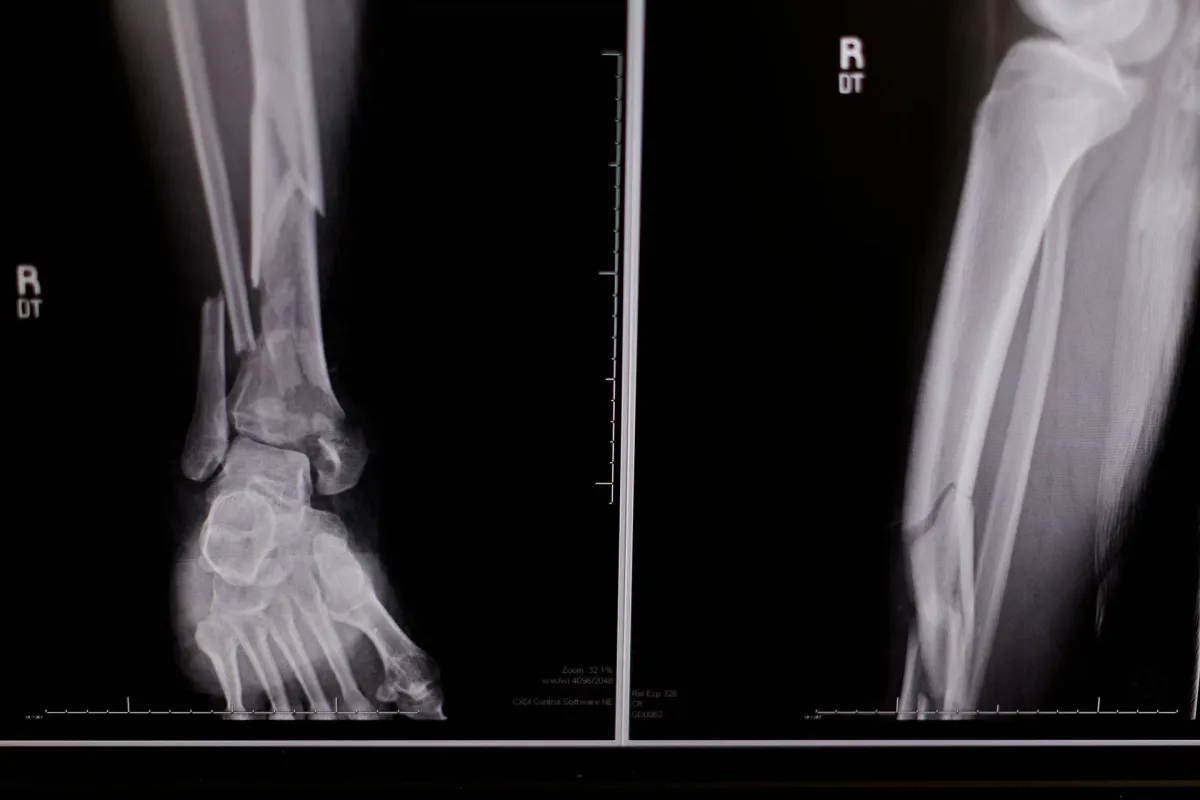

وتبين أن الأفراد الذين لديهم تاريخ من السقوط خلال العام الماضي لديهم خطر أعلى بكثير للإصابة بكسور هشاشة العظام، وكسور هشاشة العظام الكبرى، وكسر الورك.

وكان خطر الكسر المتزايد المرتبط بالسقوط السابق مستقلاً إلى حد كبير عن كثافة المعادن في العظام، ما يؤكد على الأهمية المستقلة للسقوط على أنه عامل خطر.